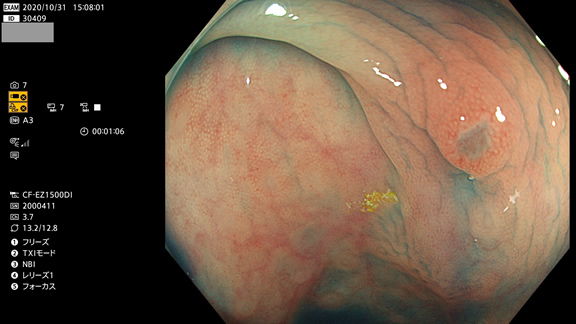

非典型的ポリープの例

粘膜の荒れにしか見えませんが、実は腺腫です(病理で確定ずみ)